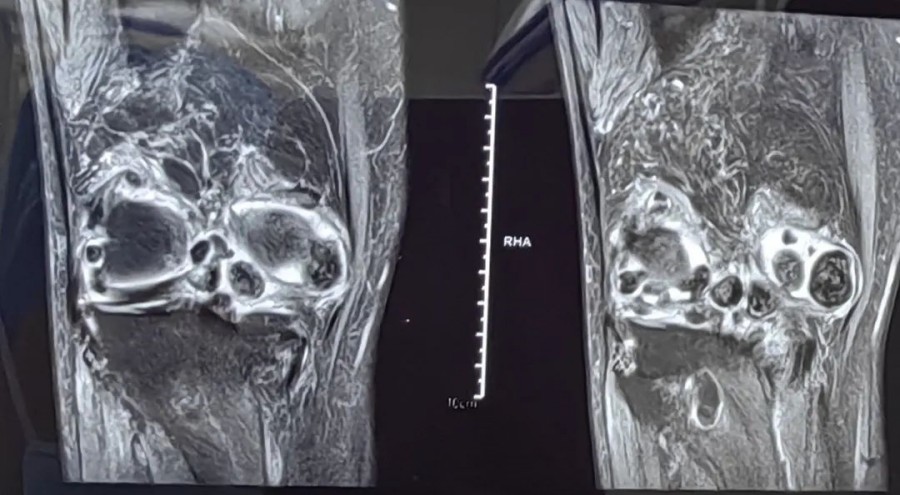

蚌埠市康复医院(市四院):腘窝滑膜软骨瘤病新选择——关节镜微创手术